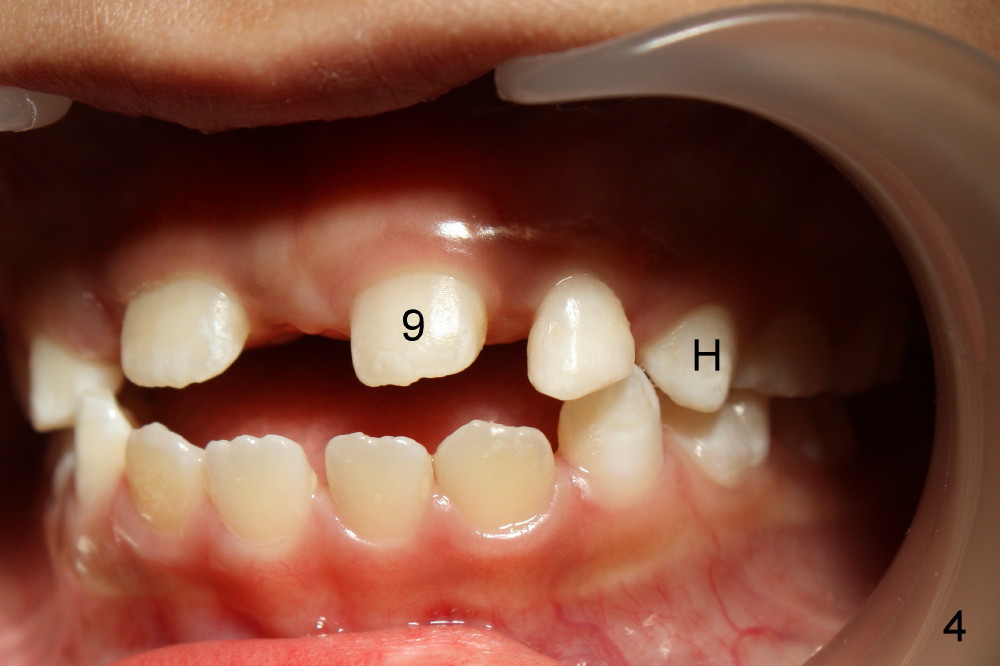

A seven-year-old co-operative boy presented to my office for composite. Exam shows open bite and a large diastema between the erupting upper central incisors (Fig.1-4). His mother notices that the diastema is more due to lateral displacement of the right central than the left central's (compare to Fig.1: black dashed line). She asks whether the uneven displacement will interfere with eruption of the upper right lateral incisor (Fig.2,3, as compared to Fig.4). She is interested in early ortho.

There are three questions. Will the right lateral erupt by itself and the diastema self corrects? When can we start ortho? How can we treat deep cingulum of #9 (Fig.2 >), removing marginal ridges or placing composite in the cingulum? The purpose of cingulum treatment is to prevent caries. Do we also need to add composite to #9 proximal surfaces to make it look as wide as #8? Thanks.

Because this child is young, I would observe for now. Measure the diastema space and the space distal to 8. Continue to observe if the eruption of 7 is closing the diastema some. It will not close it completely but there is a chance it will help. If a year from now, 7 needs more room to come in, you can do just that! No penalty for observation Xin, at least over the short term, say 6-12 months. Timothy Shaughnessy, DDS, Monday, March 25, 2013 7:21 PM